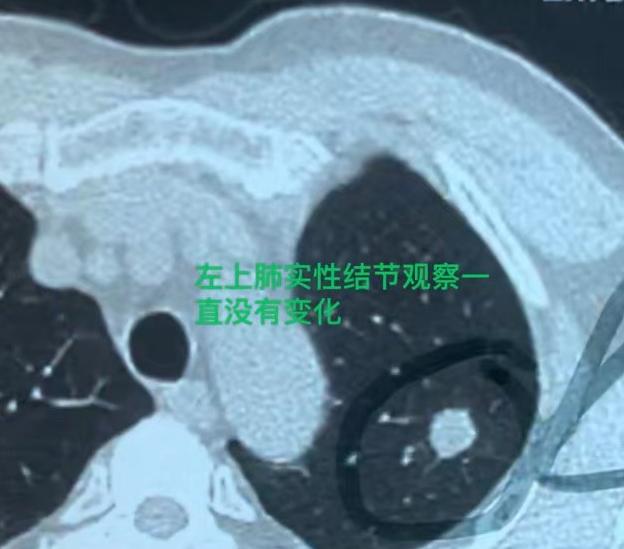

警惕!被忽视的肺实性结节,已发生转移!最近我接诊了一位66岁的男性患者,情况真的

肺结节

胸外科乔贵宾医生